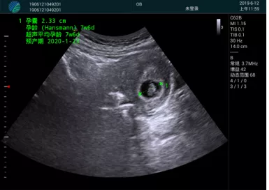

病例一:

清晰顯示孕囊,通過軟件包計算孕齡7w+6d

M20實時引導(dǎo),術(shù)中清晰顯示孕囊被破壞和抽吸針的過程,清晰顯示吸引針

抽吸結(jié)束后縱切子宮,孕囊已被完全抽吸,未見明顯殘留